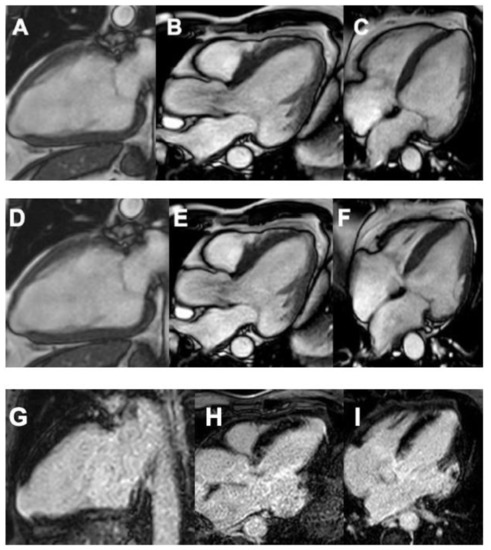

- Rochitte, C.E.; Nacif, M.S.; de Oliveira Júnior, A.C.; Siqueira-Batista, R.; Marchiori, E.; Uellendahl, M.; de Lourdes Higuchi, M. Cardiac Magnetic Resonance in Chagas’ Disease. Artif. Organs 2007, 31, 259–267. [Google Scholar] [CrossRef]

- Lee-Felker, S.A.; Thomas, M.; Felker, E.R.; Traina, M.; Salih, M.; Hernandez, S.; Bradfield, J.; Lee, M.; Meymandi, S. Value of cardiac MRI for evaluation of chronic Chagas disease cardiomyopathy. Clin. Radiol. 2016, 71, 618.e1. [Google Scholar] [CrossRef]

- Duran-Crane, A.; Rojas, C.A.; Cooper, L.T.; Medina, H.M. Cardiac magnetic resonance imaging in Chagas’ disease: A parallel with electrophysiologic studies. Int. J. Cardiovasc. Imaging 2020, 36, 2209–2219. [Google Scholar] [CrossRef]

- Rochitte, C.E.; Oliveira, P.F.; Andrade, J.M.; Ianni, B.M.; Parga, J.R.; Ávila, L.F.; Kalil-Filho, R.; Mady, C.; Meneghetti, J.C.; Lima, J.A.C.; et al. Myocardial Delayed Enhancement by Magnetic Resonance Imaging in Patients With Chagas’ Disease. J. Am. Coll. Cardiol. 2005, 46, 1553–1558. [Google Scholar] [CrossRef] [PubMed]